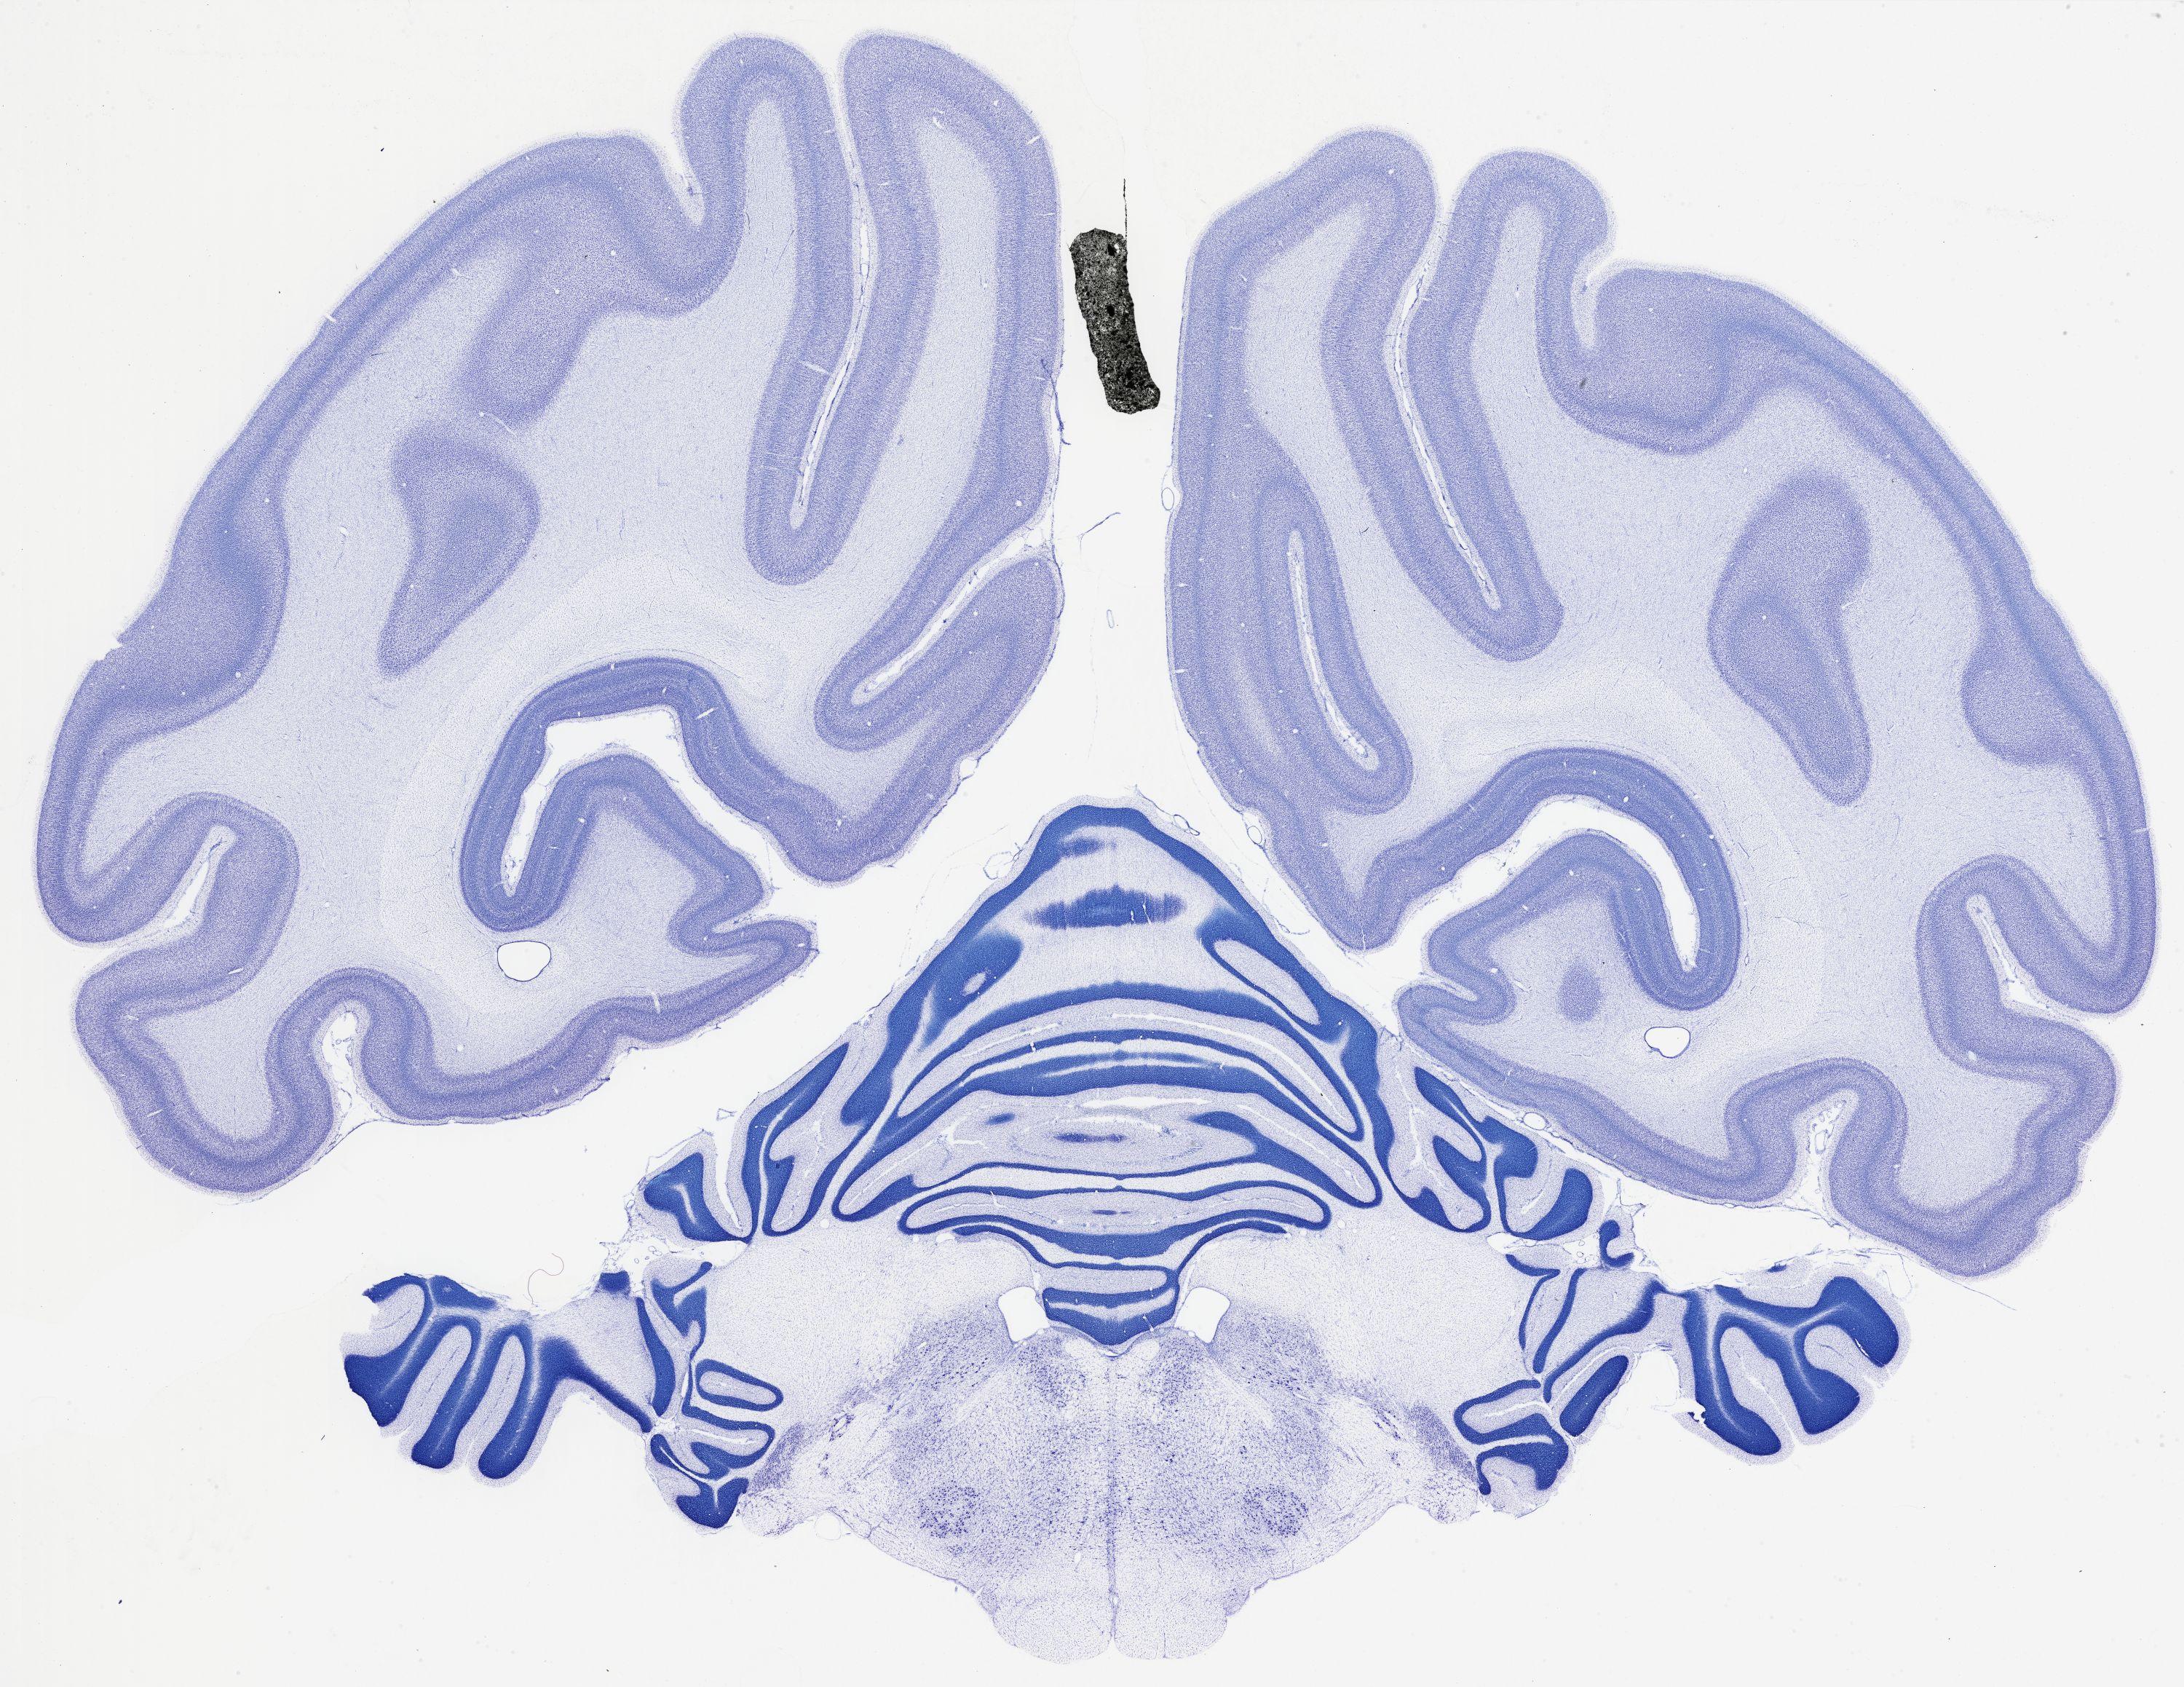

thumbnail

524